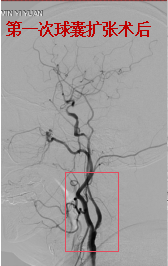

62岁女性,同样因脑梗死、左侧颈动脉狭窄入院。介入团队评估,患者颈动脉狭窄重,且远端负性重构,再灌注出血风险高,建议分期进行支架成型手术,以降低高灌注综合征发生率。两次支架成型术后,颈动脉血管重建良好,术后未发生出血等,患者平稳出院。